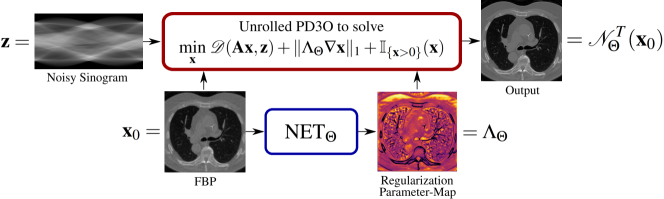

| Abstract We propose a method for fast and automatic estimation of spatially dependent regularization maps for total variation-based (TV) tomography reconstruction. The estimation is based on two distinct sub-networks, with the first sub-network estimating the regularization parameter-map from the input data while the second one unrolling iterations of the Primal-Dual Three-Operator Splitting (PD3O) algorithm. The latter approximately solves the corresponding TV-minimization problem incorporating the previously estimated regularization parameter-map. The overall network is then trained end-to-end in a supervised learning fashion using pairs of clean-corrupted data but crucially without the need of having access to labels for the optimal regularization parameter-maps. |

Here, inspired by the recent success of unrolled neural networks (NNs) [9], we consider an unrolled neural network approach in order to learn the regularization parameter . The proposed framework is summarized in Figure 1 and it is outlined next.

An unrolled NN which corresponds to an implementation of an iterative scheme of finite length is constructed to approach the solution of problem (2) assuming a fixed regularization parameter-map. Within the unrolled NN, the regularization parameter-map is estimated from the input data via a sub-network and is used throughout the whole reconstruction scheme. To be more precise, given some initial estimate we work with an iterative scheme (speficied in the next section)

Here, denotes a U-Net [10] with learnable parameters . We denote by the overall resulting network, i.e.

The unrolled NN can then be end-to-end trained in a supervised manner on a set of input-target image-pairs. This resulting network can be identified as a pipeline that combines in a sequential way 1) the estimation of the regularization parameter-map which is adapted to the data (and hence in medical imaging to the new patient) and 2) the iterative scheme that solves the image reconstruction problem.